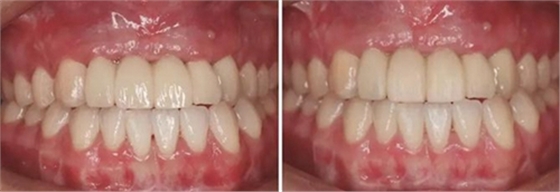

圖35 預(yù)粘接 圖36 戴入全瓷修復(fù)體正面觀

圖37 戴入全瓷修復(fù)體局部舌側(cè)觀 圖38 永久修復(fù)后微笑

圖39 永久修復(fù)后大笑

③患者試戴個(gè)性化氧化鋯基臺(tái),檢查基臺(tái)就位情況,咬合狀況,基臺(tái)邊緣位于齦緣下<1mm,試戴氧化鋯基底,確認(rèn)基底就位良好,邊緣密合,完成永久修復(fù)體的制作。口內(nèi)戴入氧化鋯基臺(tái)后,扭矩扳手加力至30N后,聚四氟乙烯封閉螺絲通道,樹脂封孔。試戴全瓷修復(fù)橋體,檢查冠邊緣與基臺(tái)邊緣緊密接觸,與周圍軟硬組織相協(xié)調(diào),確認(rèn)鄰接以及修復(fù)體顏色良好。調(diào)整咬合,靜態(tài)咬合:正中咬合時(shí)后牙區(qū)均勻接觸,輕咬合時(shí)前牙區(qū)無(wú)接觸,重咬合時(shí)輕接觸,無(wú)牙合干擾或早接觸;動(dòng)態(tài)咬合:側(cè)方運(yùn)動(dòng)時(shí)尖牙引導(dǎo)或前牙組牙功能的交錯(cuò)保護(hù)牙合,前伸運(yùn)動(dòng)是切牙引導(dǎo)牙合,工作側(cè)和非工作側(cè)無(wú)牙合干擾。咬合調(diào)整完畢后高度拋光,口外用硅橡膠制備預(yù)粘接代型,超聲振蕩修復(fù)體,消毒后使用自粘接樹脂水門汀于口外預(yù)粘接并戴入口內(nèi),使用牙線去除多余粘接劑。拍攝X線片,確認(rèn)基臺(tái)和牙冠完全就位。

3、通過制作個(gè)性化轉(zhuǎn)移桿,將種植體周圍軟組織的形態(tài)輪廓精確地復(fù)制并轉(zhuǎn)移到模型上,個(gè)性化制作的氧化鋯基臺(tái)及全瓷修復(fù)體,生物相容性及美學(xué)效果良好,患者對(duì)最終修復(fù)效果滿意。